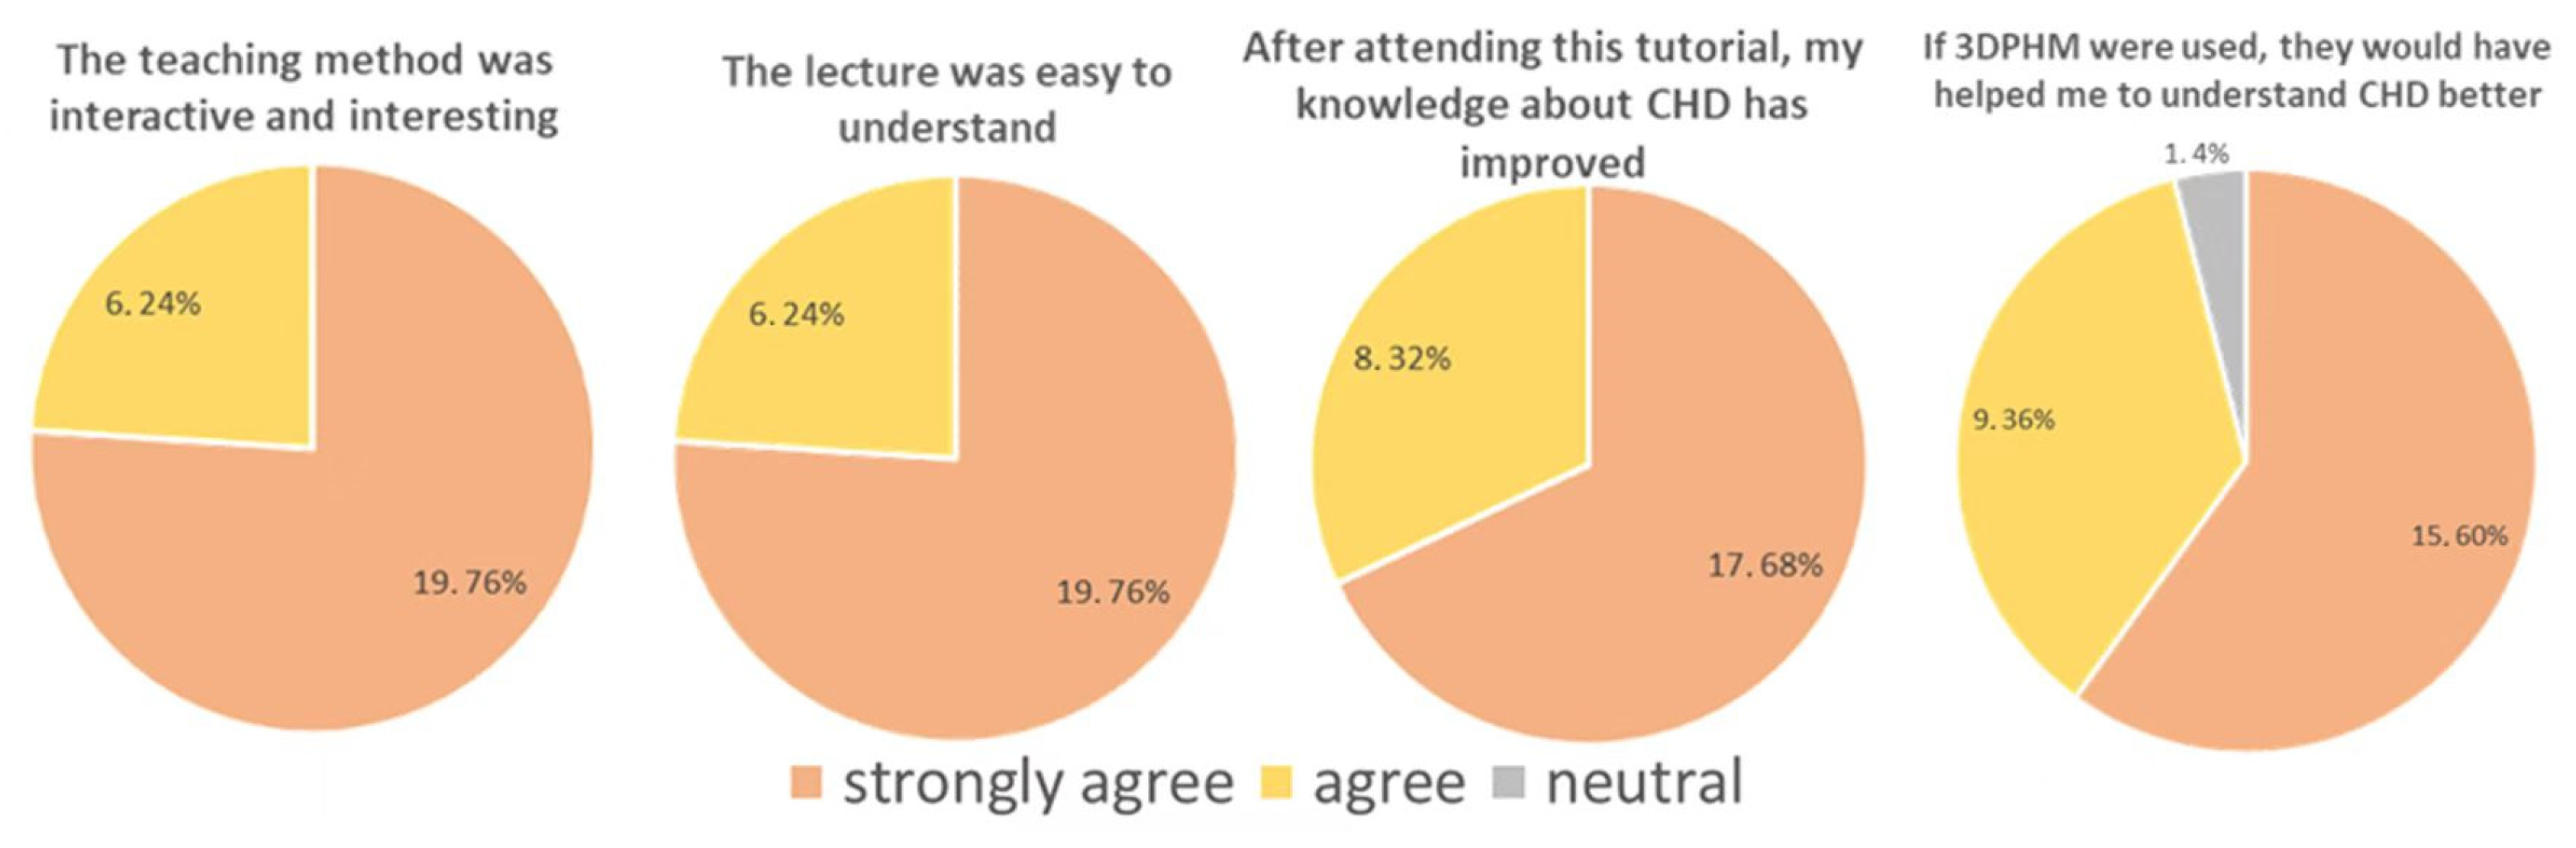

4.2. 3D-Printed CHD Models in Medical Education

- Karsenty, C.; Guitarte, A.; Dulac, Y.; Briot, J.; Hascoet, S.; Vincent, R.; Delepaul, B.; Vignaud, P.; Djeddai, C.; Hadeed, K.; et al. The usefulness of 3D printed heart models for medical student education in congenital heart disease. BMC Med. Edc. 2021, 21, 480. [Google Scholar] [CrossRef]

- Lau, I.; Sun, Z. The role of 3D printed heart models in immediate and long-term knowledge retention in medical education. Rev. Cardiovasc. Med. 2022, 23, 022. [Google Scholar] [CrossRef]